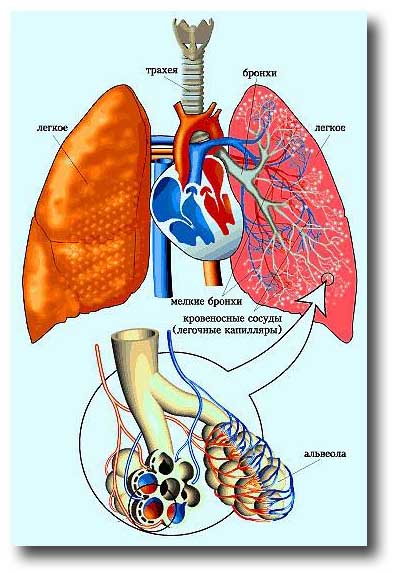

Схема дыхательной системы человека: а — общий план строения; б — строение альвеол; 1 — носовая полость; 2 — надгортанник; 3 — глотка; 4 — гортань; 5 — трахея; б — …

Дыхательные пути представляют собой систему трубок, просвет которых формируется благодаря наличию в них костей и хрящей . Внутренняя поверхность дыхательных путей …

Дыхательнаясистемачеловекасостоитизтканейиорганов,обеспечивающихлегочную вентиляциюилегочноедыхание .К воздухоносным путям относятся: нос, полость носа, носоглотка, …

Дыхательная система выполняет жизненно важную функцию — обеспечение клеток организма кислородом и освобождение их от углекислого газа, являющегося конечным продуктом …

Дыхательная система (дыхательный аппарат), systema resperatorium, состоит из дыхательных путей и парных дыхательных органов - легких . Дыхательные пути …

Основной механизм регулирования дыхания — центральная нервная система . Дыхательный центр регулирует частоту и ритм дыхания .